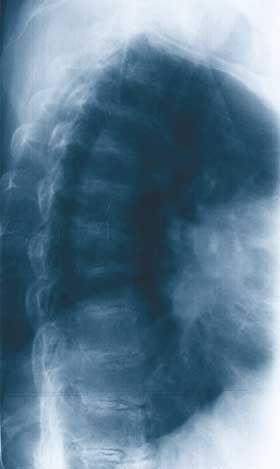

A 54-year-old man presented with a 3-year history of non-inflammatory pain in his lower back, and his hip and knee joints. He also had black discolouration of the palms, cheeks and sclerae (Box 1A) and his urine turned black on alkalinisation (Box 1B). Spinal x-rays showed intervertebral disc calcification (Box 1C). A diagnosis of alkaptonuria (ochronosis) was made.

![]() A: Discolouration of the sclerae. ![]() B: Urine sample before (left) and after (right) alkalinisation. ![]() C: Spinal x-ray showing intervertebral disc calcification. |